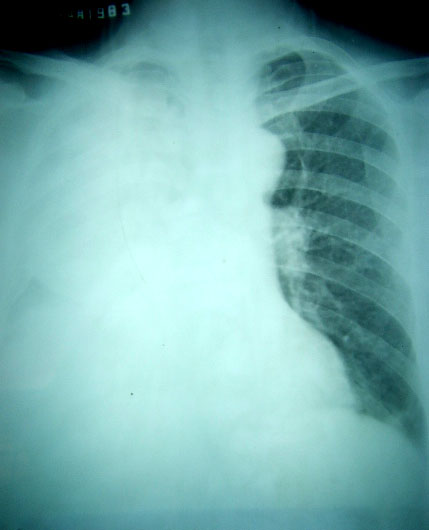

以下是引用software在2007-5-18 19:48:00的发言:[br]患者男,因发热,咳嗽,咳痰半月余而入院,有盗汗,双手会不自主的颤抖。 [br][br]这是第一张片:[br][br]明摆着是胸腔积液,还有胸膜肥厚,入院后行胸穿,抽出淡褐色胸水,生化检查,我只记得糖0.8,其它的不记得了,李凡他(+)。 [br][br]第二天复查胸片,就成这模样了。。。。。 [br]